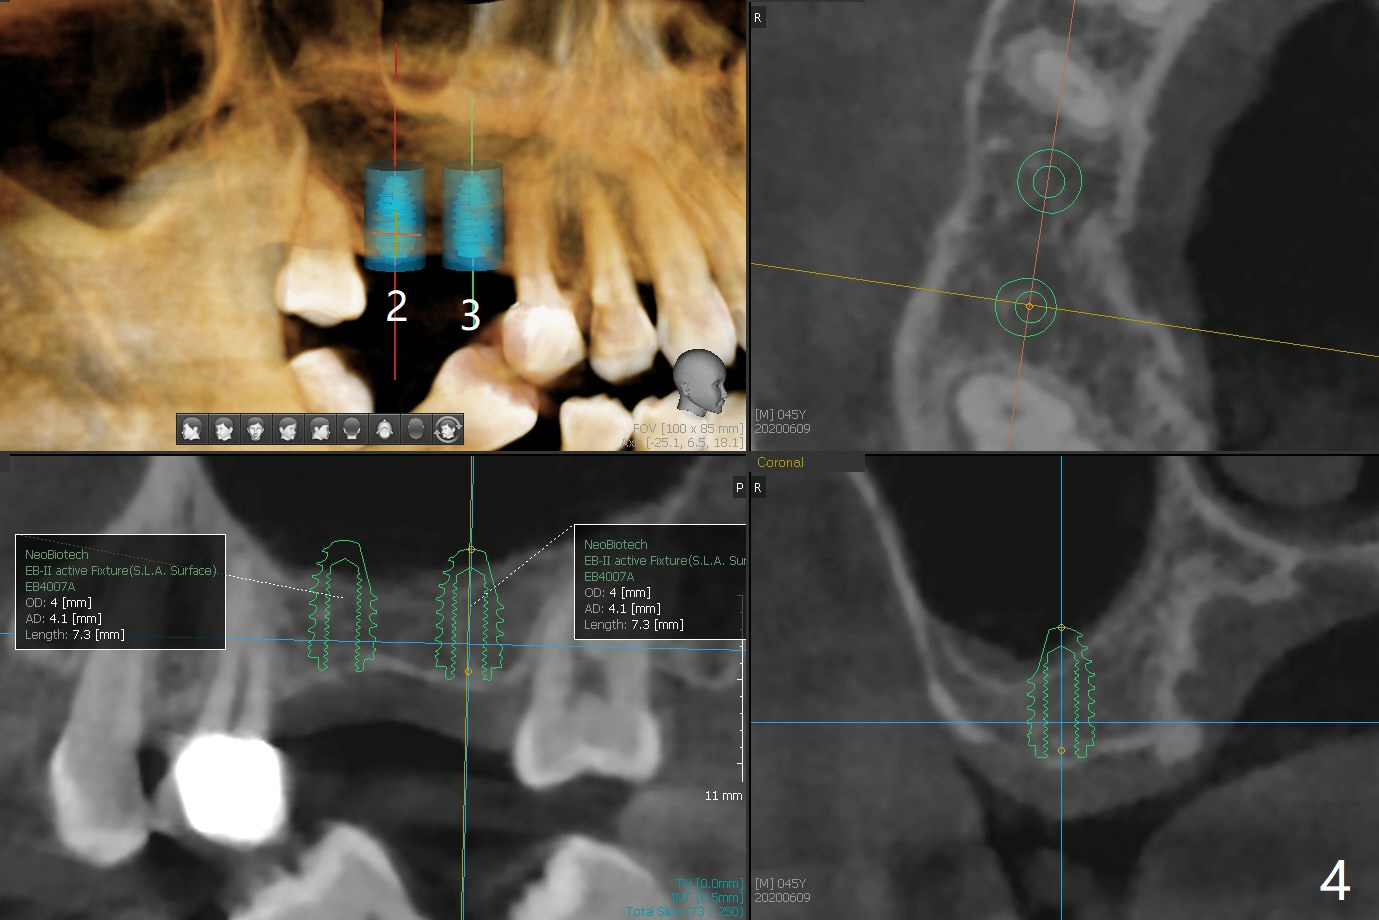

A 45-year-old man requests extraction of #19 because of endodontist's diagnosis of root fracture (Fig.1). CT shows typical apical periodontitis (Fig.2) without sign of root fracture (profilogram, data not shown), although the buccal plate of the mesial root is lost (Fig.3). Ideally 2 implants should be placed in UR and LR quadrants to prevent #19 root fracture after RCT (Fig.4). Alternative way is to place an implant at #3 (5x7.3 mm) and #30 immediately after #31 extraction. In fact a surgical guide for #30 will be fabricated resting the distal aspect of the tilted tooth #31 after sectioning the mesial portion in the lab (Fig.1 red line).